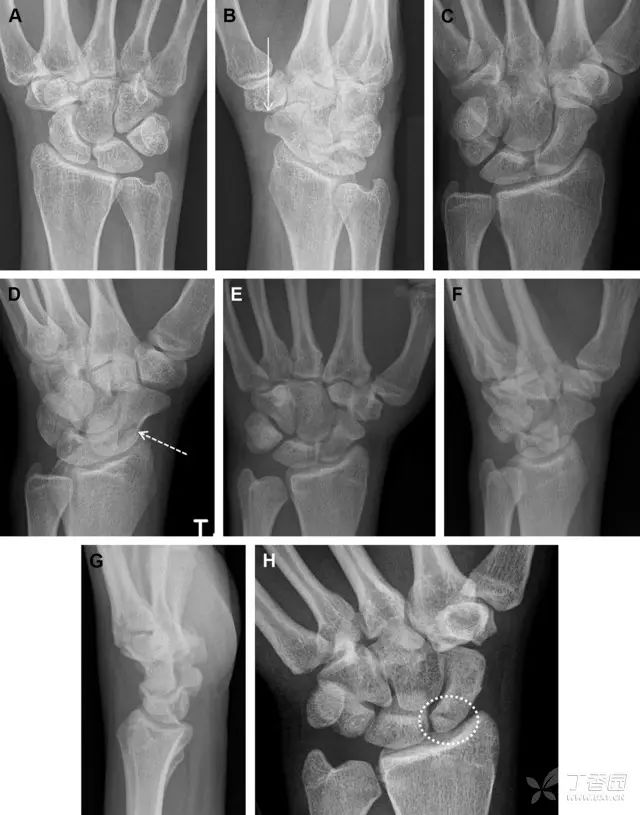

腕掌关节骨折脱位为高能量损伤,常伴有神经损伤。腕掌关节组成骨多,侧位片上重叠遮挡多,骨折不易发现,容易漏诊。在前后位片上,关节面不平滑、关节间隙不对称、关节皮质破坏、关节面重叠常提示腕掌关节骨折脱位。特别是第 4、5 腕掌关节脱位,在前后位片上不容易发现;该损伤不稳定,也称为「变异型拳击手损伤/骨折」。

图 4 第 4、5 腕掌关节骨折脱位。(A)正常腕掌关节,关节面平衡起伏、平行;前后位(B)、斜位(C)、侧位(D),第 5 掌骨近端附近软组织肿胀(白色箭头),冠状面关节面重叠,背侧撞击剪切应力致钩状骨骨折(*),在前后位及斜位片上可见双密度影。第 4 掌骨底部可见微小骨折碎片(D,虚线箭头),第 4、5 掌骨掌侧成角。(E~G)变异型拳击手损伤:第 4、5 掌骨背侧脱位而未见骨折(E,虚线方框),钩状骨有骨折小碎片(F,短虚线箭头),第 4 掌骨基底部关节内骨折(G,长虚线箭头)